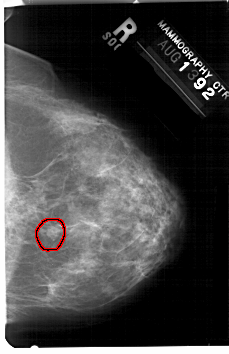

FILE: A_1434_1.RIGHT_CC.OVERLAY

TOTAL_ABNORMALITIES 1

ABNORMALITY 1

LESION_TYPE MASS SHAPE OVAL MARGINS CIRCUMSCRIBED

ASSESSMENT 4

SUBTLETY 4

PATHOLOGY BENIGN

TOTAL_OUTLINES 1

BOUNDARY